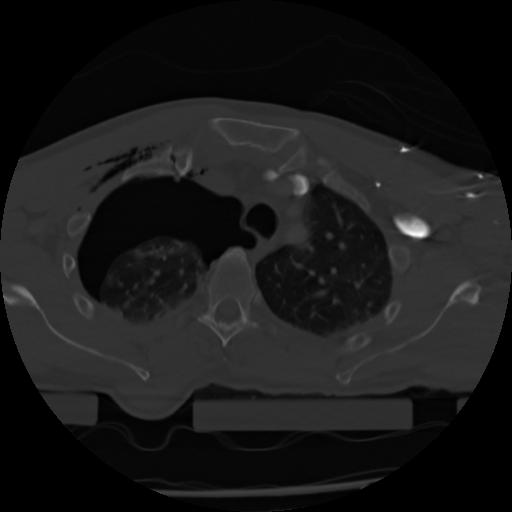

21 ANGIO,CE,Axial,3.0,ANGIO,,